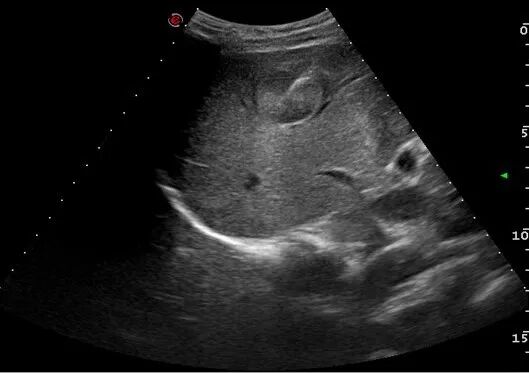

在超声的实时引导下应用穿刺针或活检枪经皮刺入肿块内,获取细胞或组织标本。 ①疾病诊断 明确肿瘤的良恶性、明确肿瘤的组织学来源和分型、鉴别原发肿瘤或转移性肿瘤。 ②指导治疗方案 对取得的标本进行免疫组化、基因检测,指导靶向、免疫或化疗药物选择。 ③肿瘤的局部治疗 通过该技术可将抗肿瘤药物(如溶瘤病毒)直接注射到实体瘤内;囊性的肿瘤也可通过该技术进行穿刺引流减轻压迫症状。 ①创伤小 伤口仅如针孔大小。 ②安全 操作时间短,并发症少,耐受性好。 ③报告准确迅速 现场评价取材满意度,第二天即可获得细胞病理报告。 ④花费低 减轻家庭负担。 ①肝脏占位 ②胰腺占位 ③腹盆腔占位 ④浅表肿块 ⑤肿大淋巴结等 穿刺活检针的针芯外层设计为保护套管,切取肿瘤组织后,套管将肿瘤组织封闭在针芯内,隔离了肿瘤组织和正常组织接触的机会,避免种植转移。